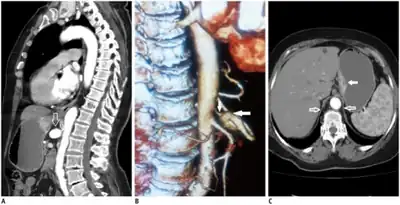

Further evaluation and confirmation can be obtained via angiography to investigate the anatomy of the celiac artery.[5] Historically, conventional angiography was used, although this has been largely replaced by less invasive techniques such as computed tomography (CT) and magnetic resonance (MR) angiography.[2][5] Because it provides better visualization of intra-abdominal structures, CT angiography is preferred to MR angiography in this setting.[5] The findings of focal narrowing of the proximal celiac artery with poststenotic dilatation, indentation on the superior aspect of the celiac artery, and a hook-shaped contour of the celiac artery support a diagnosis of MALS.[2] These imaging features are exaggerated on expiration, even in normal asymptomatic individuals without the syndrome.[2]

Proximal celiac artery stenosis with poststenotic dilatation can be seen in other conditions affecting the celiac artery.[2] The hook-shaped contour of the celiac artery is characteristic of the anatomy in MALS and helps distinguish it from other causes of celiac artery stenosis such as atherosclerosis.[2] This hooked contour is not entirely specific for MALS however, given that 10–24% of normal asymptomatic individuals have this anatomy.[2]

Median arcuate ligament syndrome-a)Stenosis and aneurysm of celiac artery because of compression arrows b)severe stenosis and poststenotic dilatation white arrow c) median arcuate ligaments arrows and gastric mucasal thickening -

Coeliacus compression